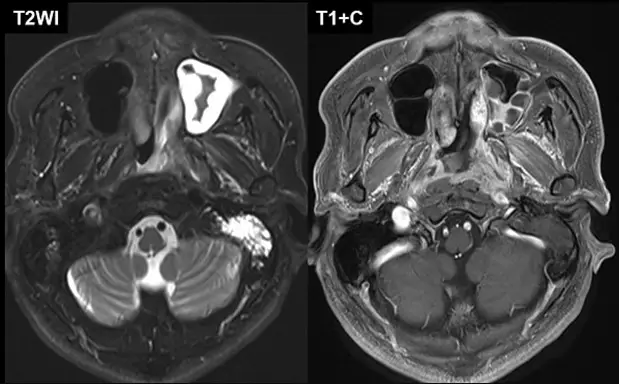

本題提供兩張 MRI 影像,分別為 T2WI (左圖) 與 T1+C (右圖,打藥後):

左圖 (T2WI - 橫切面):

- 左側乳突氣房 (Left Mastoid Air Cells):呈現高訊號 (亮白色)。正常的乳突氣房應充滿空氣,呈現黑色 (signal void)。此處的高訊號代表內部充滿液體,即乳突積液 (Mastoid effusion) 或中耳積水。

- 左側上頷竇 (Left Maxillary Sinus):前方可見左側上頷竇也呈現極高訊號,顯示有鼻竇炎或液體滯留(這在 NPC 病人中常見,因腫瘤可能阻塞鼻道或耳咽管開口附近的淋巴引流,但非絕對特異)。

- 鼻咽部 (Nasopharynx):左側鼻咽壁相較於右側顯得飽滿、不對稱。

右圖 (T1+C - 橫切面,顯影劑增強):

- 左側鼻咽部 (Left Nasopharynx):在左側 Fossa of Rosenmüller (羅氏窩/側隱窩) 區域,可見一個明顯的顯影軟組織腫塊 (Enhancing soft tissue mass)。

- 解剖關聯:此腫塊的位置剛好位於耳咽管 (Eustachian tube) 開口的後上方。腫塊壓迫或阻塞了耳咽管,導致中耳通氣不良,負壓產生並引發液體滲出,進而形成左圖所見的乳突/中耳積水。

- 對比右側:右側的 Fossa of Rosenmüller 結構清晰,呈現正常的凹陷狀。

綜合判斷:左側鼻咽腫塊 + 左側中耳/乳突積水 = 典型鼻咽癌表現。

- 影像特徵:MRI 顯示腫瘤位於好發部位 (Fossa of Rosenmüller),並伴隨同側乳突積水 (Mastoid effusion)。這完全符合 NPC 的診斷。

- T2WI 高訊號 在乳突/中耳 = 積水 (Effusion)。

- T1+C 強化腫塊 在鼻咽側壁 = 腫瘤本體。

- 確認兩者之因果關係 (腫瘤阻塞耳咽管 積水)。